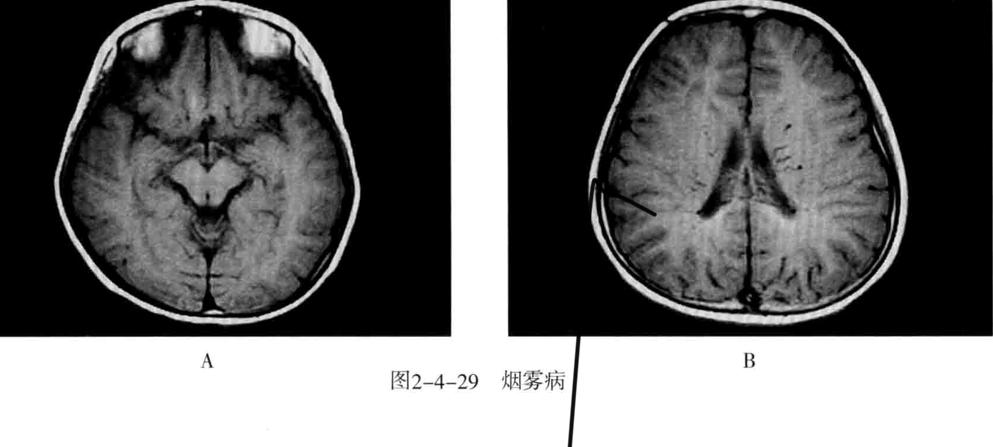

十、烟雾病

又称为脑底异常血管网症、脑底动脉环闭塞症。是以脑内虹吸段至大脑前、中动脉近端狭窄或闭塞,同时伴有广泛侧支循环形成,导致颅底出现异常毛细血管网为特征的脑血管病。好发年龄10岁以下和40-50岁。临床表现为脑缺血和脑出血两大类。儿童多为颈内动脉系统缺血性改变,成人多为颅内出血。

- CT平扫表现为双侧额叶、顶叶及颞叶皮质或皮质下区多发脑梗死及脑萎缩改变,也可以出现颅内出血。增强有时可见到颈内动脉及大脑前中动脉粗细明显不对称,或者充盈不良,甚至不显影。可显示基底池及基底节区的侧支循环网,大多表现为为不规则的扭曲成团的强化血管影。

- MRI表现为脑缺血引起的T1WI低、T2WI高信号脑梗死区,颈内动脉及大脑中动脉主干的“流空效应”变弱或消失,异常血管网在T2WI上表现为基底节区和鞍上池内多发细小血管影,呈网状低信号或无信号区。皮质侧支循环形成时,增强扫描可见皮质血管增多、扩张、强化、呈“常春藤征”。

- MRA可直接显示颈内动脉、大脑前、中动脉狭窄或闭塞,于颅底见烟雾状异常血管网,常可见到颈外动脉和椎-基底动脉分支代偿性增粗。